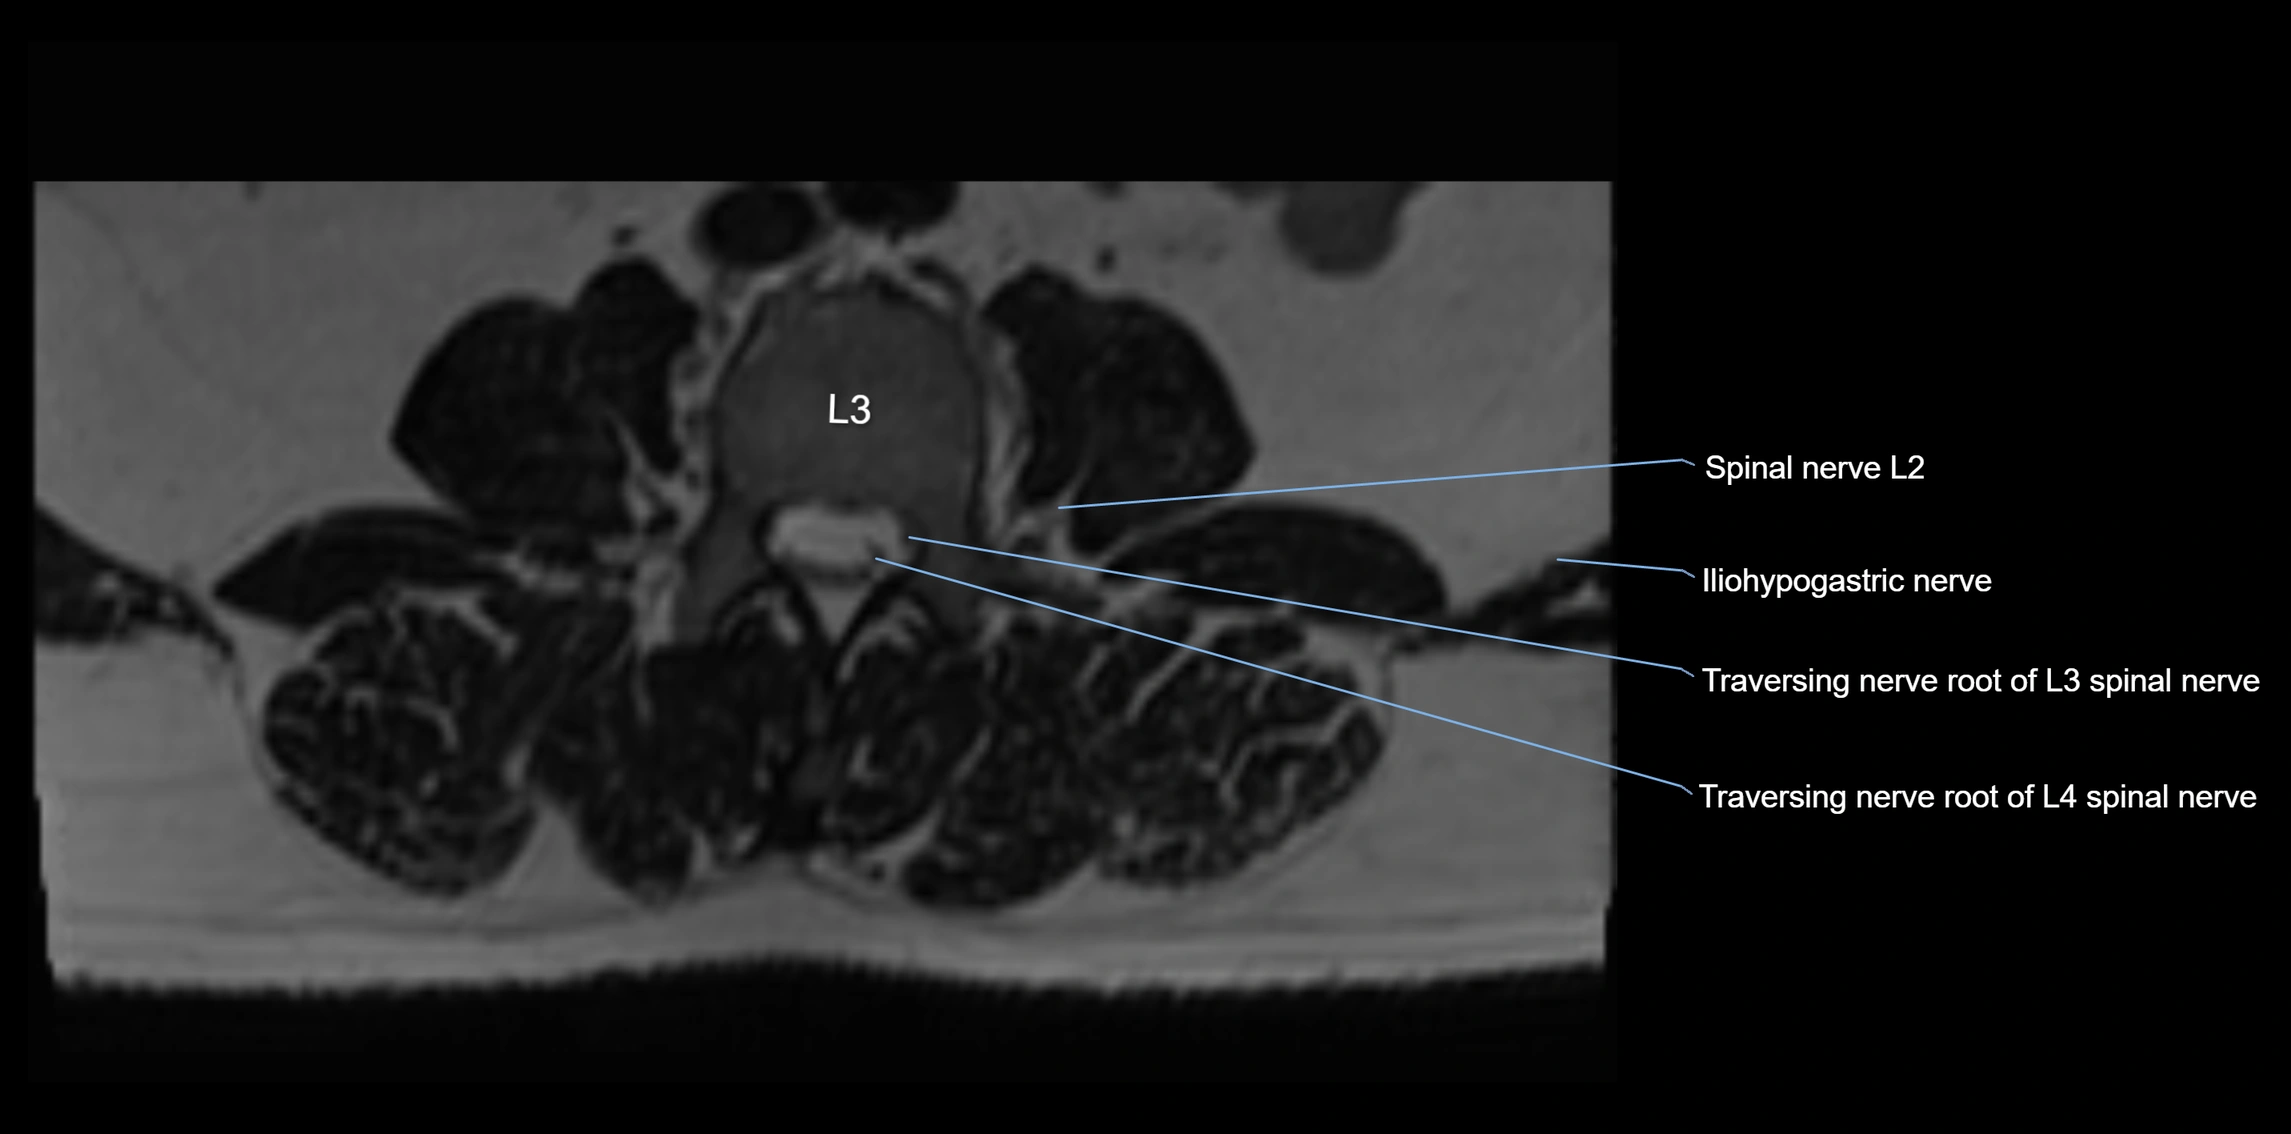

MRI image

image